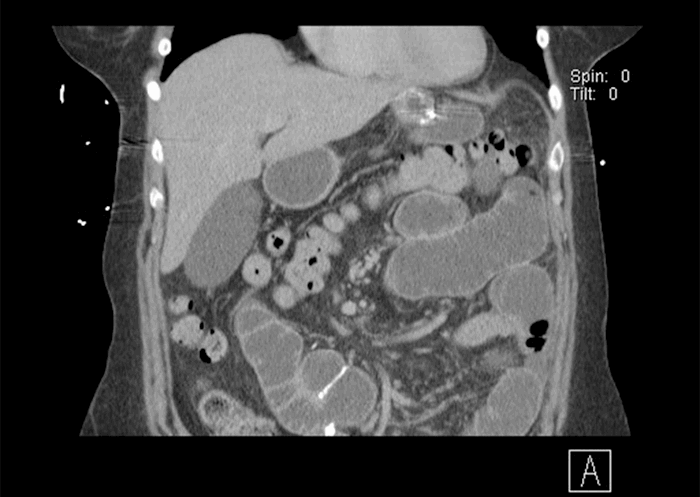

A 60-year-old female patient presented to the emergency room complaining of nausea and vomiting for three days, along with right upper quadrant (RUQ) abdominal pain. The patient described the RUQ pain as a gnawing, spasm-type pain that became severe at the time. The patient then underwent an ultrasound of the RUQ, which revealed mild dilation of CBD at upper limits of normal, no gallbladder wall thickening, and no cholelithiasis. Patient was also sent for an abdominal X ray (Figure 1) and CT of the abdomen and pelvis (Figure 2), which showed a partial distal small bowel obstruction (pSBO) with a normal gallbladder.

Figure 1. Abdominal X-Ray in ER, showing pSBO